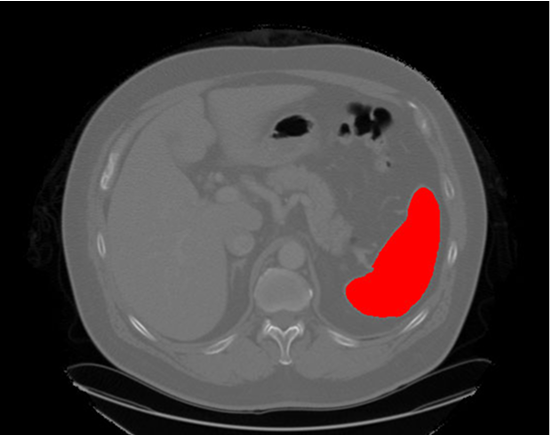

- CNNs (Convolutional Neural Networks) and U-Net are widely adopted for identifying structures, segmenting organs, and detecting anomalies with minimal error.

- High-quality annotated data fuels accurate AI models, allowing researchers to train algorithms effectively for multiple imaging modalities like MRI, CT, and PET.

AI-powered imaging detects tumours at early stages, helping oncologists create patient-specific treatment plans.